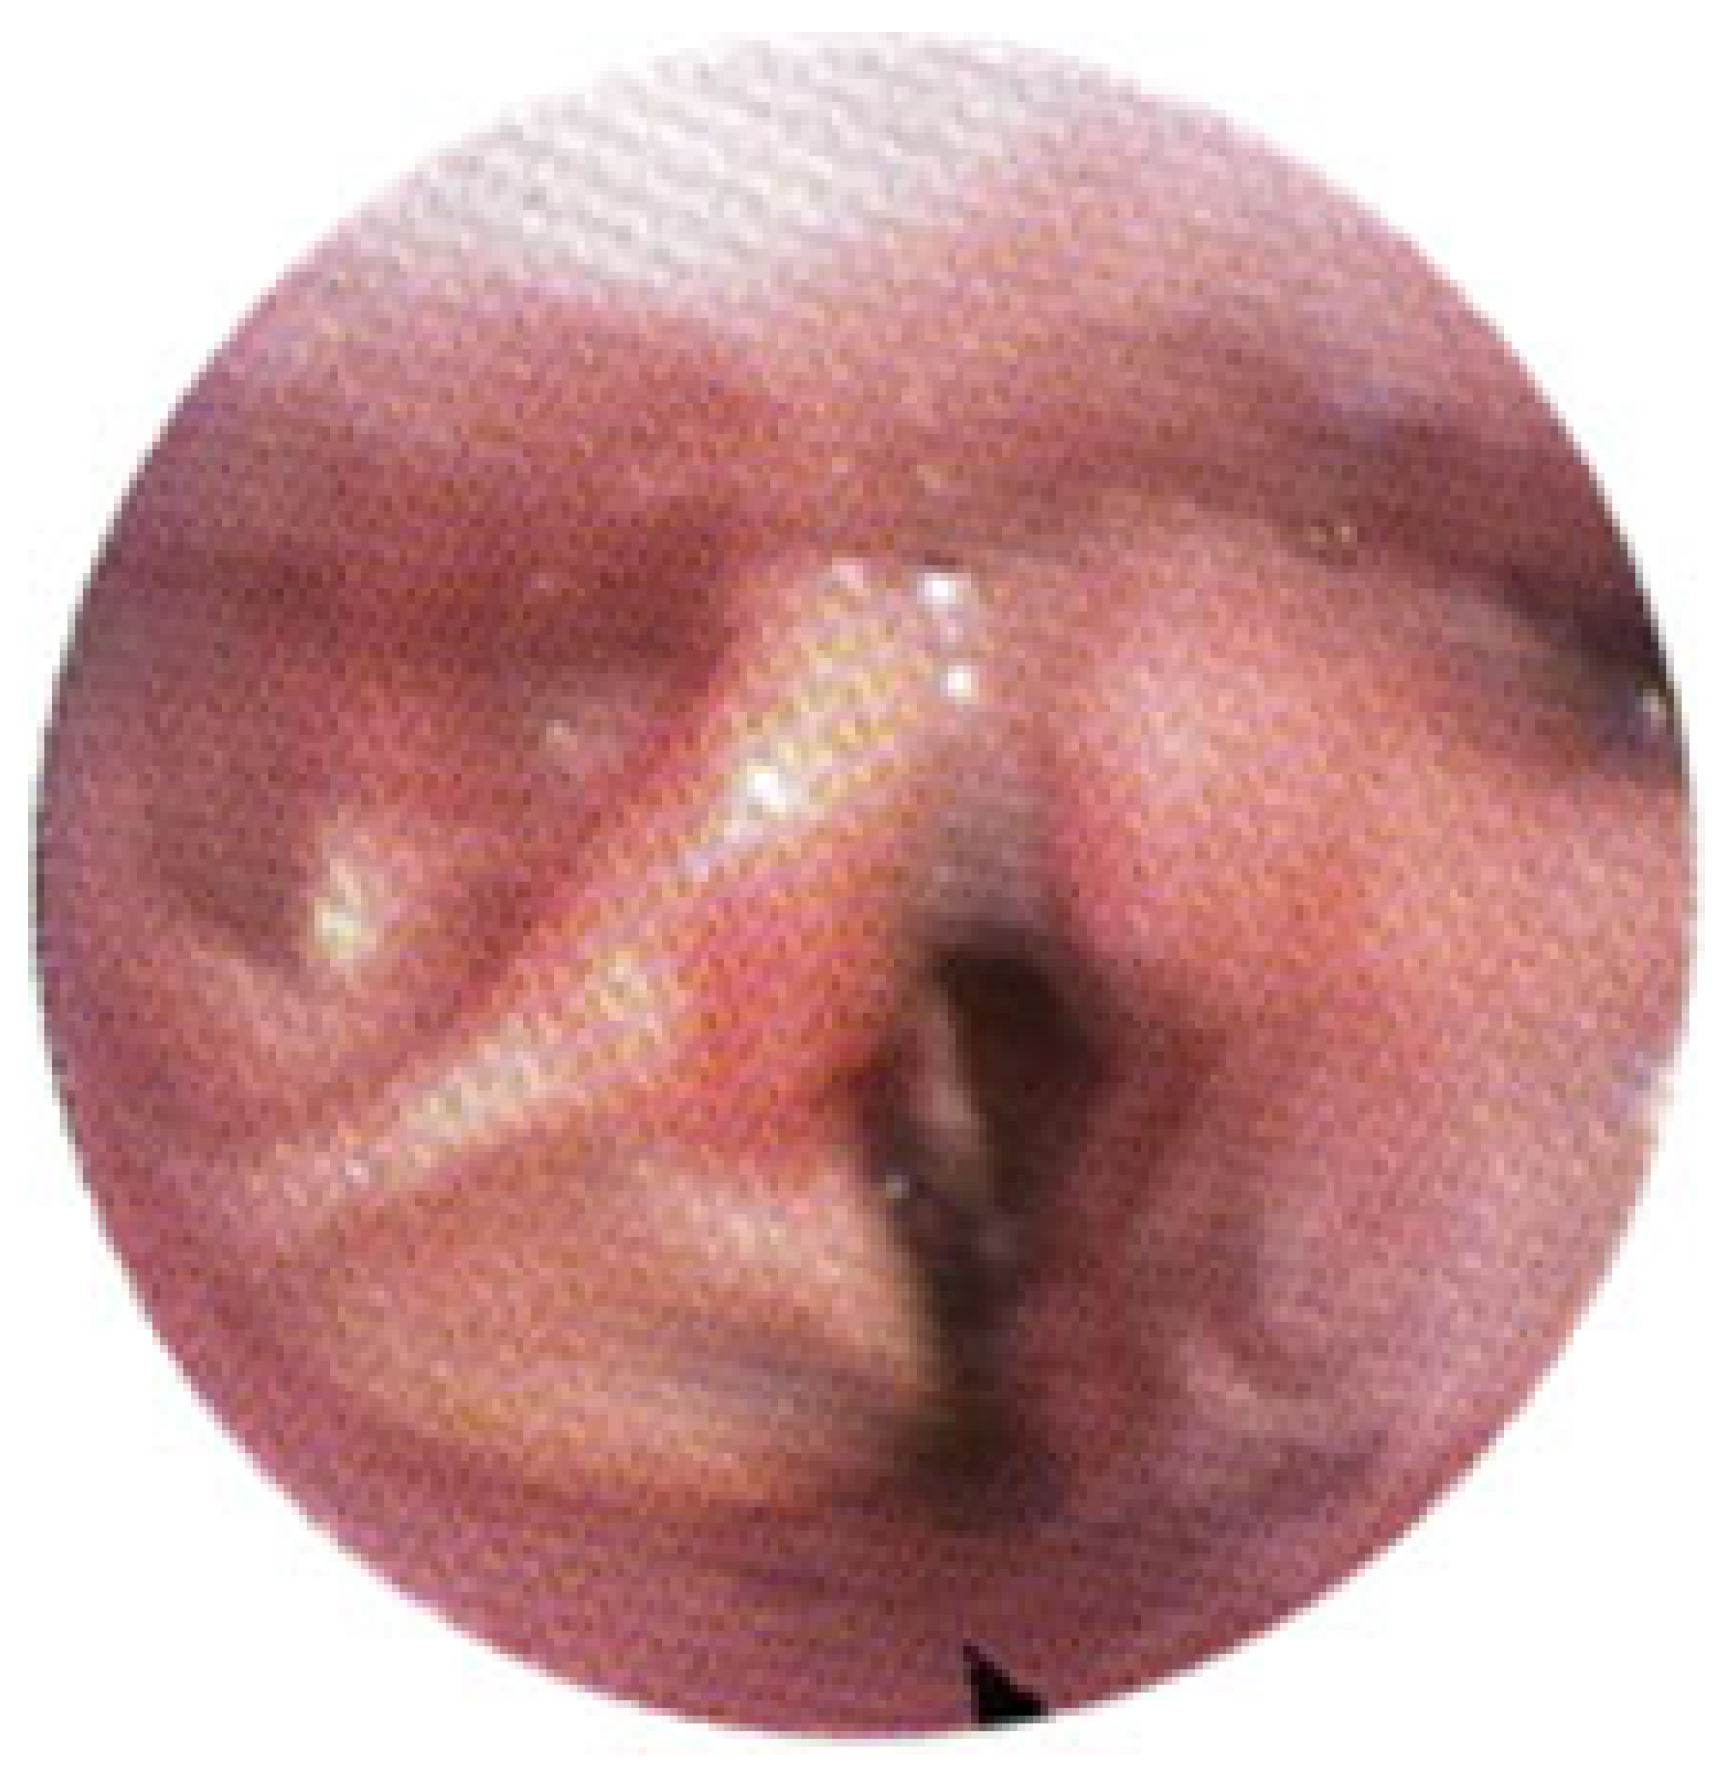

3.1. Magnetic Resonance Imaging (MRI) Findings